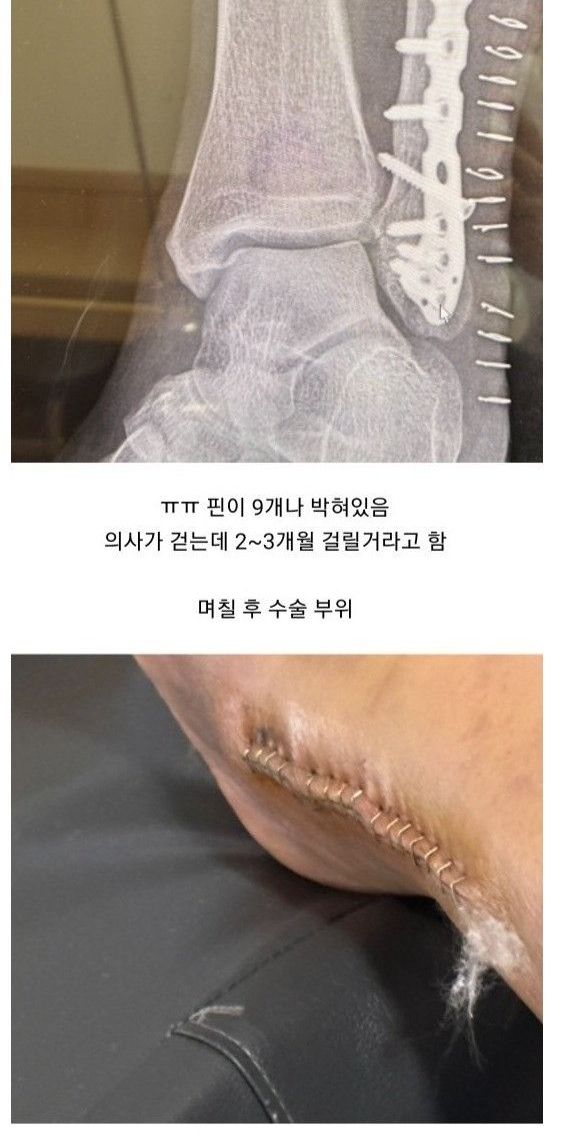

빙판길에서 자빠져 발목 부러져서 수술

수술했는데 하나도 안아픔

한달 뒤 멀쩡하게 걸어다녀서 나중에 의사가 보고 화들짝

병원직원들한테 박수받음